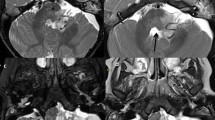

MRI of a medulloblastoma (grade IV) in a 4-year-old boy. Axial T2-W image (a), contrast-enhanced axial T1-W image (b), axial diffusion-weighted image (c) and corresponding ADC map (d). This solid tumour is T2 isointense to gray matter and enhances inhomogeneously. The lesion has uniformly restricted diffusion consistent with its hypercellular nature